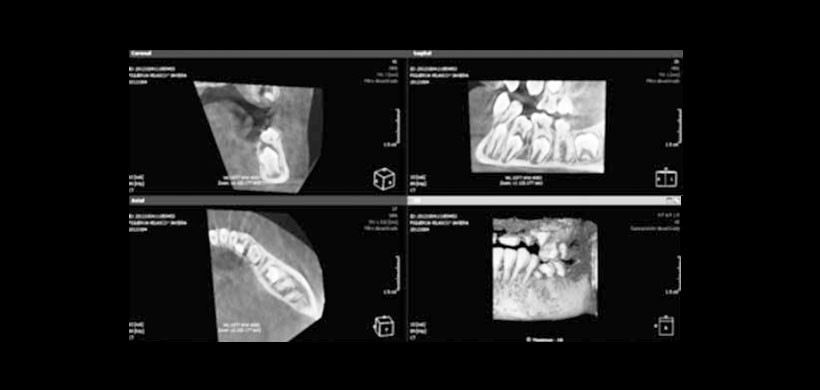

Se solicita como examen complementario una tomogra a computada cone beam, donde se descarta la anquilosis del diente 7.4 (Figura 3).

En este paciente se puede evidenciar las graves consecuencias que suceden al no tratar las infraoclusiones en forma oportuna y adecuada, asi mismo se resalta la importancia de la imagenologia 2d y en especial la 3D para una evaluacion mas precisa y sertera.